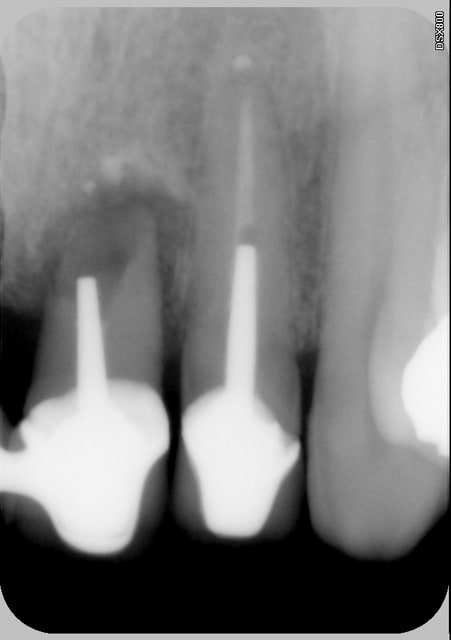

C'est quoi la proba d'avoir une deuxième bio à 5 canaux en 2 semaines?

(la radio excentrée est dégueulasse, mais ça montre les doubles courbures, quelques peu minimisées par l'angulateur...